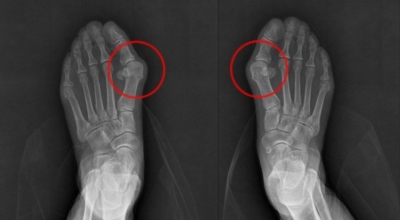

3. 엄지발가락 통증 - 무지외반증

우리에게 잘 알려져 있는 엄지발가락 통증의 원입니다. 선천적 요인으로 인한 발병보다는 하이힐, 뾰족구두, 키높이 깔창과 같이 앞이 좁고 엄지발가락에 자극이 심한 신발 유행으로 후천성 환자가 늘어나고 있습니다. 체중 증가나 류마티스 관절염도 무지외반증의 원인입니다. 엄지발가락이 둘째 발가락으로 휘어지면서 대측으로 회전해서 제1중족 관절이 안쪽으로 돌출되는 무지외반증은 서있거나 걸어 다닐때 신발과 마찰해 통증과 염증이 발생합니다.